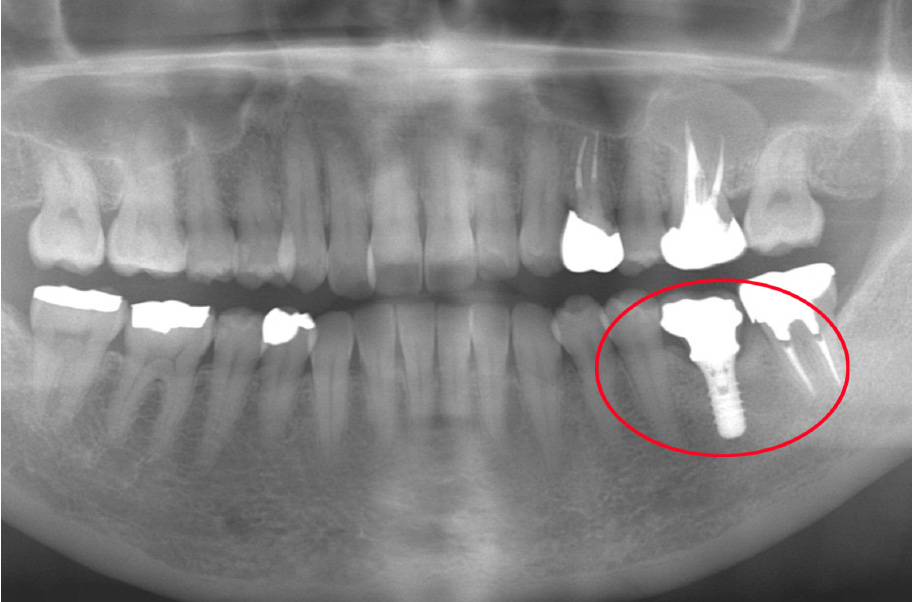

【16年後】

2025年3月56歳

治療から16年が経過しましたが、インプラントは非常に良い状態で安定しており、噛み合わせも問題ありません。

特筆すべきは、「インプラントがしっかりと噛む力を引き受けてくれたおかげで、 他のご自身の歯への負担が減り、この16年間でさらに歯を失うことがなかった」という点

現在も3~4ヶ月ごとに定期メンテナンス(パウダーによるクリーニング)に通って